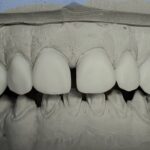

E-Max

L’E.max®, 100% céramique, est à base de disilicate de lithium, reconnu pour sa haute résistance à la flexion (500 Mpa).

Elle est donc une alternative esthétique aux restaurations céramo-métalliques, conservant, ensemble, éclat et durabilité.

Couronne, bridge de 3 éléments, inlay, onlay, facette